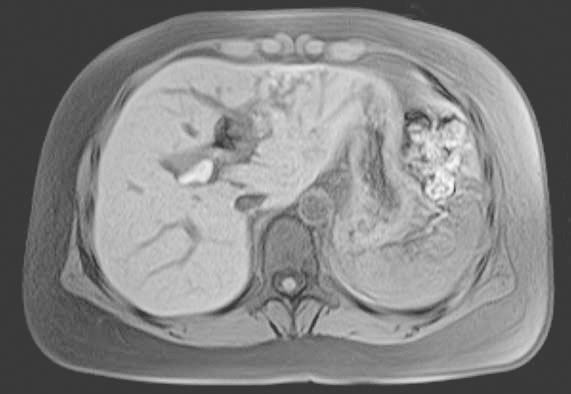

(8)增强CT(2018年1月):术后改变,术区胆管结构紊乱;肝内胆管扩张积气;左右肝管区小片状较高密度影(图4)。

图4 增强CT(2018年1月)